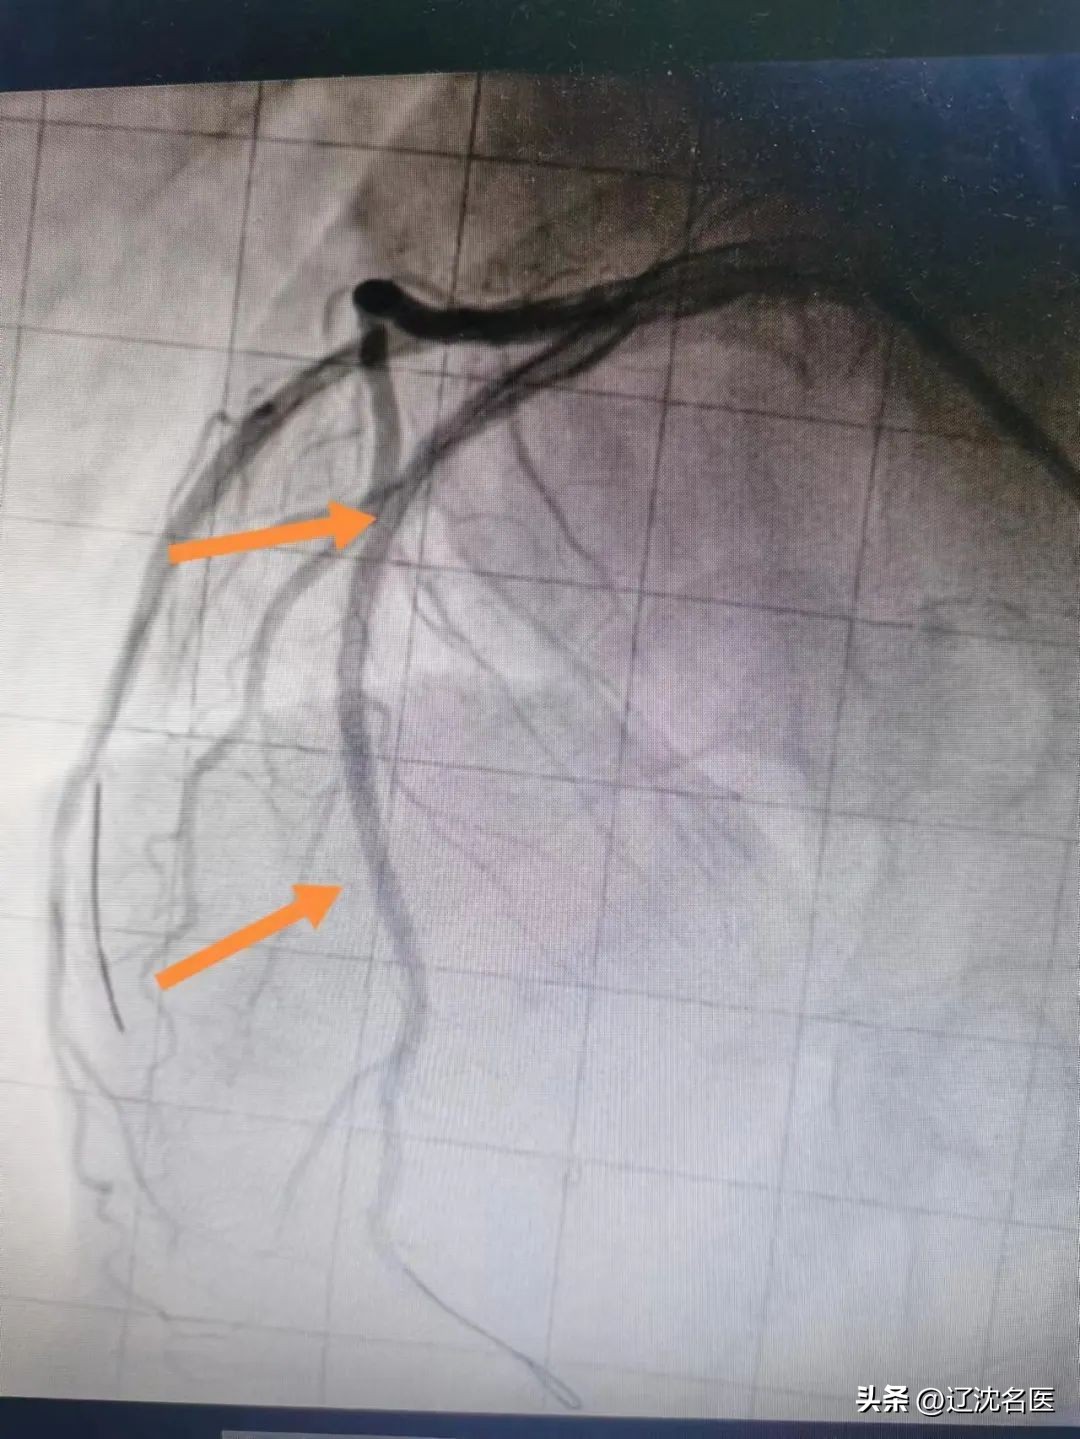

由于患者特殊的生理结构,左冠状动脉位于心脏右侧,右冠状动脉位于心脏左侧,冠状动脉造影时,X线投照体位选择,导管送入冠脉开口的旋转动作应与一般患者的常规操作相反。加之,右位心易合并其他心脏畸形,或发生血管变异和走行异常 。

15时34分,患者被推入导管室,虽然已经做了术前评估和心理准备,但一到实操,大家还是如履薄冰。在佟主任带领下,团队充分发挥协作精神,改变惯有思维,谨慎操作。冠脉造影示:主要血管LAD开口90%狭窄,狭窄后100%闭塞,佟主任经慎重考量,经冠脉内溶栓及血栓抽吸,最后在LAD中远端置入支架一枚,血管顺利开通,TIMI血流3级,患者转危为安,大家如释重负。